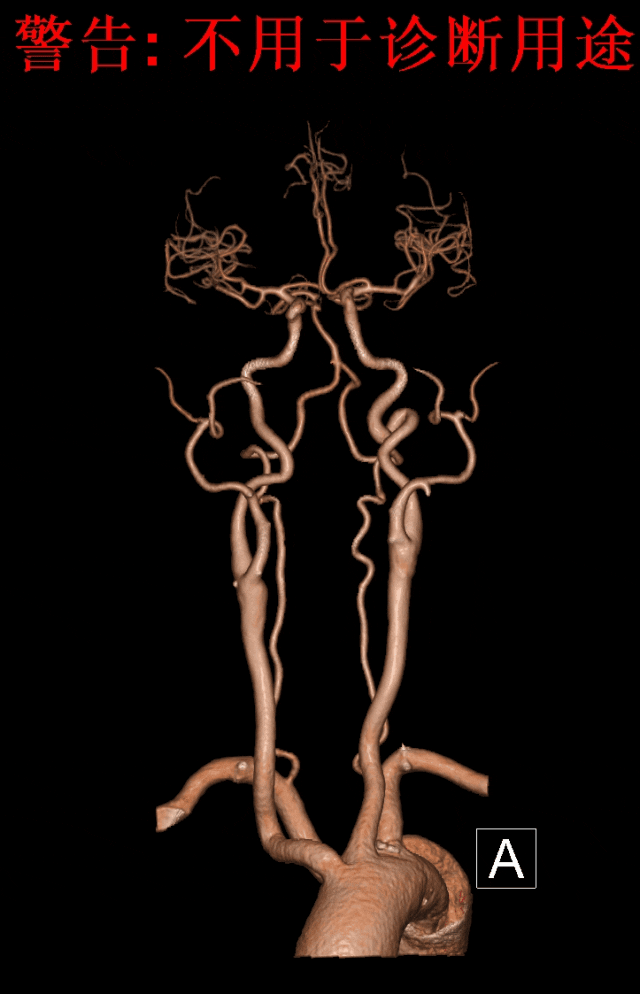

术后随访:

6个月后再次随访,CTA影像图显示血管形态良好,血管支架通畅。